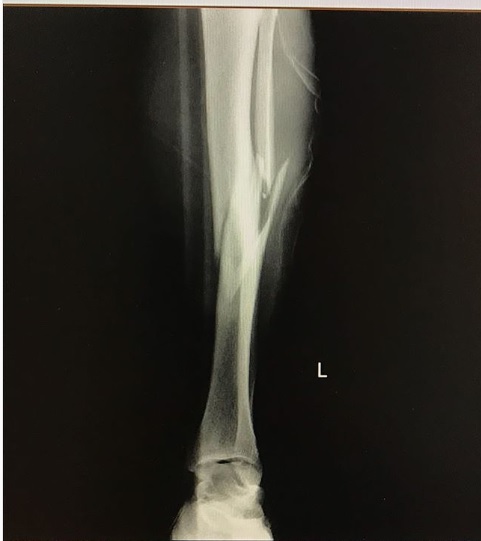

Luego de que su tabla se trabara, y su cuerpo diera un giro de 360°, el modelo argentino terminó con una rotura de tibia y peroné. “Creo que fue el peor dolor que he sentido”, reveló en su cuenta de Instagram.

Mediante su cuenta de Instagram, Ferres compartió con sus seguidores, capturas de las ecografías su pierna, donde se pueden apreciar las graves roturas que sufrió en dos huesos de su pierna izquierda.

Maxi Ferres | Instagram